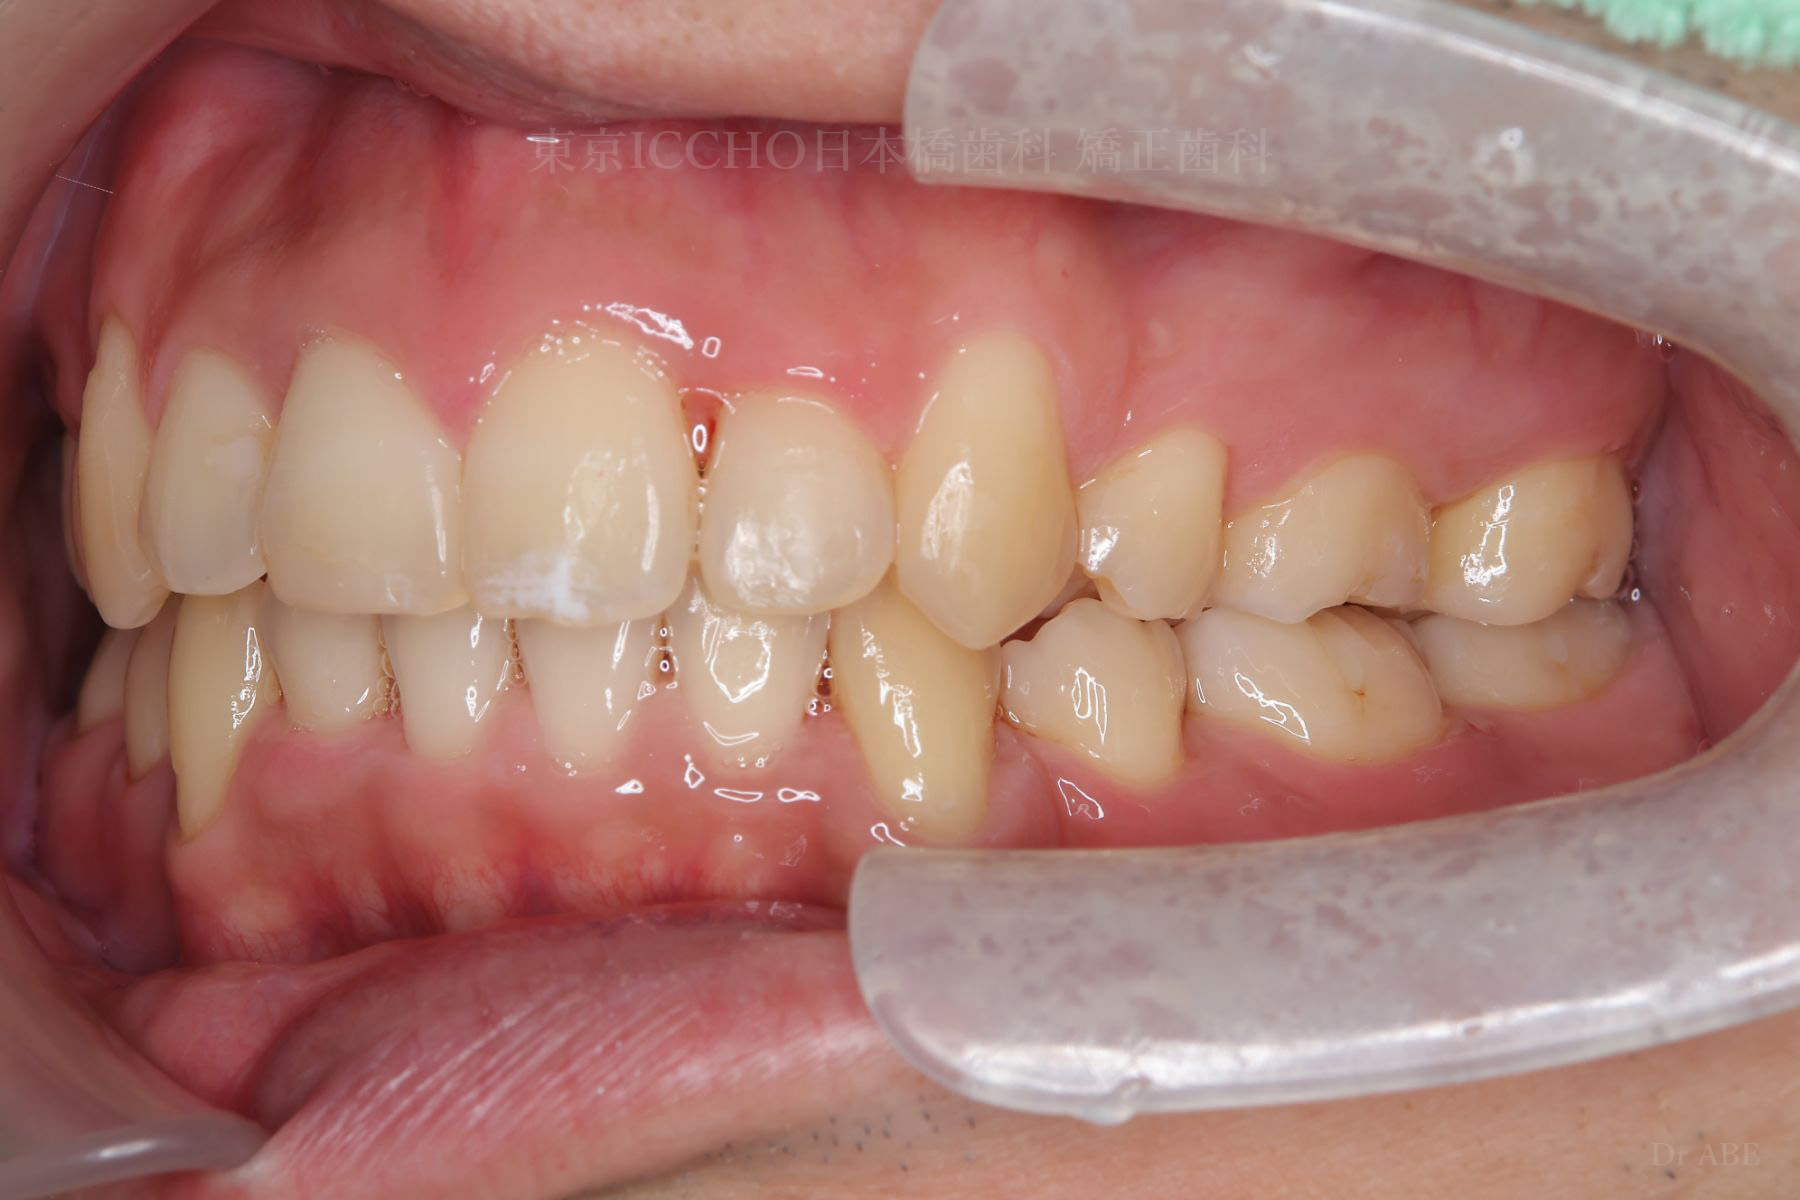

治療前

主訴 前歯が噛めないこと、出ているのを直したい。

治療内容 かみ合わせの不正と顎が小さいため、上下左右第一小臼歯4本の抜歯を行い前歯を後ろへ下げた。

また、前歯が噛まない状態のため、かみ合わせを少し下げて噛むように誘導し、全体的にかみ合わせとして機能的な矯正治療を行った。